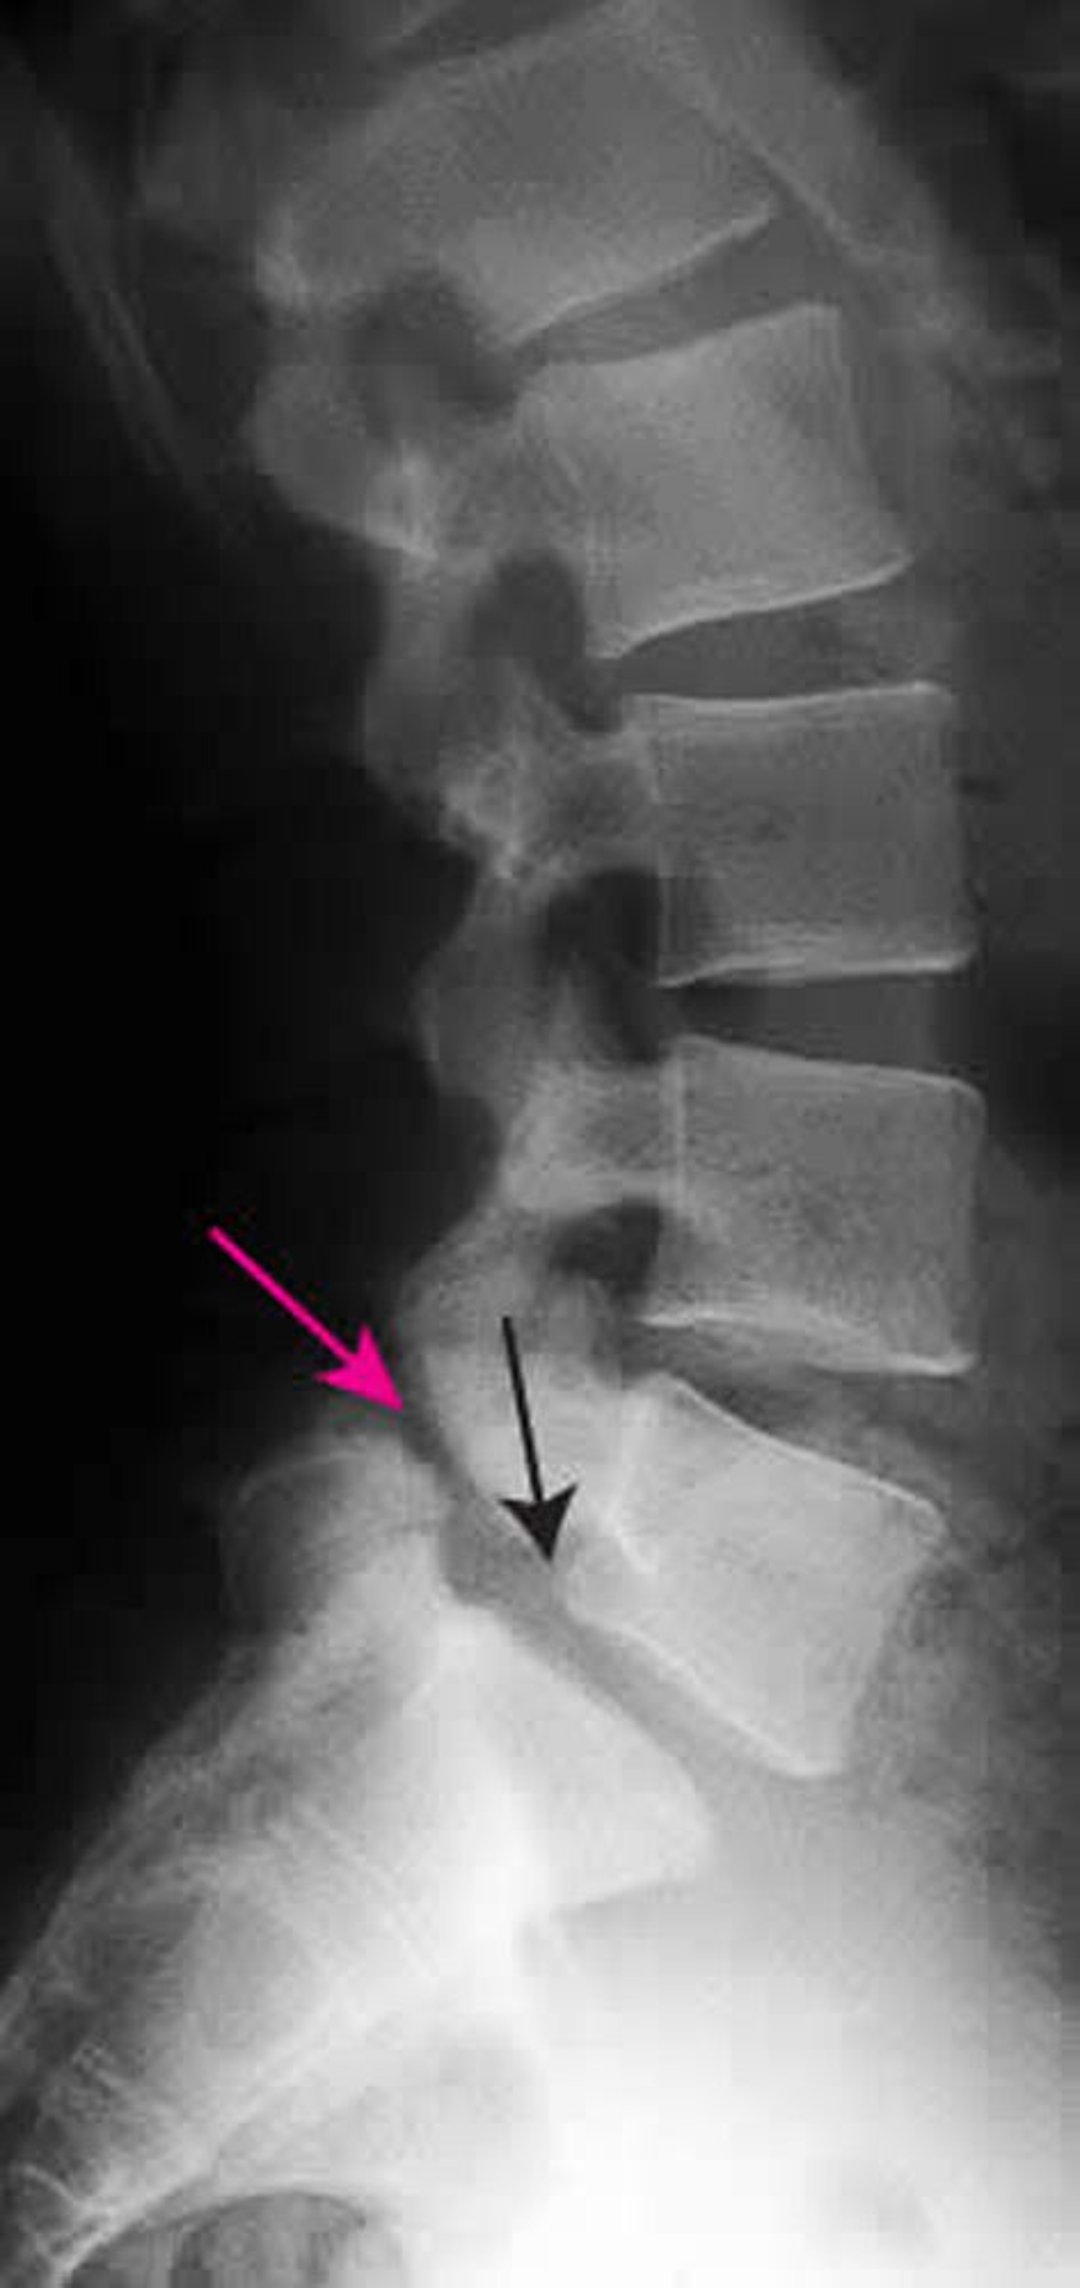

спондилолистез

Этот рентгеновский снимок показывает спондилолистез 1 степени L5 на S1. Черная стрелка показывает заднюю границу L5, которая смещена к переди от S1. Красная стрелка указывает на спондилолизис (дефект в межсуставной части).